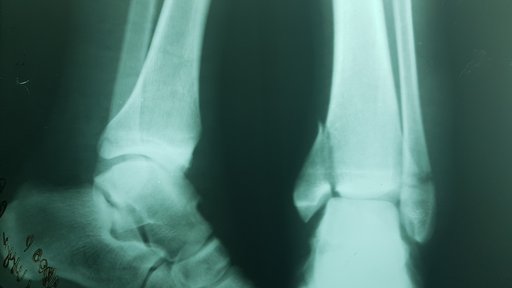

Хвора Л. 45 р. отримала травму в побуті на сходах. Через 30 хв після травми доставлена родичами в травмпункт КНП ТМКЛШД. Оглянута травматологом травмпункту, направлена на рентгенографію. Згідно даних рентгенограм встановлено діагноз: Закритий с\3 – н\3 лівої м\гомілкової кістки зі зміщенням уламків. Закритий перелом внутрішньої кісточки та заднього краю лівої в\гомілкової кістки зі зміщенням. Розрив ДМГС зліва. Підвивих стопи до зовні та до заду.

Хвора О. звернулася в травмпункт КНП ТМКЛШД через 5 години після травми яку отримала в побуті при падінні зі стільця. Оглянута травматологом травмпункту, направлена на рентгенографію. Згідно даних рентгенограм встановлено діагноз: Закритий перелом обох кісточок правої гомілки та заднього краю в\гомілкової кістки зі зміщенням уламків. Розрив ДМГС справа. Хворій накладено тимчасову фіксацію та направлено в приймальне відділення КНП ТМКЛШД. Хвора повторно оглянута травматологом стаціонару. При огляді відмічається виражений набряк, біль, порушення функції н\кінцівки. Встановлено діагноз : Закритий перелом обох кісточок правої гомілки та заднього краю в\гомілкової кістки зі зміщенням уламків. Розрив ДМГС зліва. Оскільки на момент огляду у хворої відмічався незадовільний стан м’яких тканин хворій було запропоновано проміжне оперативне втручання з фіксацією г\ступневого суглобу в АЗФ або проміжне лікування системою скелетного витяжіння. При госпіталізації проведено необхідні інструментальні та лабораторні методи обстежень. Хвора відмовилася від накладання АЗФ. Вибрано метод лікування скелетним витягом. Під час перебування у відділенні хвора отримувала протинабрякову терапію, знеболюючі препарати, антикоагулянти. На 8-му добу лікування скелетним витягом набряк спав, м’які тканини перебували в задовільному стані. Хворій проведено демонтаж ССК. Та проведено оперативне втручання: Відкрита репозиція з МОС перелому зовнішньої кісточки пластиною LCP та відкрита репозиція з МОС внутрішньої кісточки спицею та гвинтом. Фіксація ДМГС позиційним гвинтом. Після оперативного втручання хвора переведена в палату. З 2-3 доби хворій дозволено активні рухи у г\ступневому суглобі без навантаження на праву н\кінцівку. Шви знято на 12 добу, хвора в задовільному стані з наданими рекомендаціями щодо тактики подальшого лікування та реабілітації виписана з травматологічного відділення.

Хворий М. 39 р. звернувся в травмпункт КНП ТМКЛШД через 40хв після травми яку отримав в побуті при неправильному приземленні під час стрибку. Оглянутий травматологом травмпункту, направлена на рентгенографію. Згідно даних рентгенограм встановлено діагноз: Закритий перелом обох кісточок правої гомілки зі зміщенням уламків. Хворому накладено тимчасову фіксацію та направлено в приймальне відділення КНП ТМКЛШД. Повторно огляд. травматологом стаціонару. При огляді відмічається незначний набряк, біль, порушення функції н\кінцівки. Встановлено діагноз : Закритий перелом обох кісточок правої гомілки зі зміщенням.